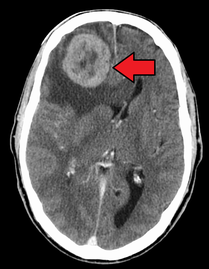

Initially, nearby lymph nodes are struck early.[9] The lungs, liver, brain, and bones are the most common metastasis locations from solid tumors.[9]

Metastatic tumors are very common in the late stages of cancer. The spread of metastasis may occur via the blood or the lymphatics or through both routes. The most common sites of metastases are the lungs, liver, brain, and the bones.[10]